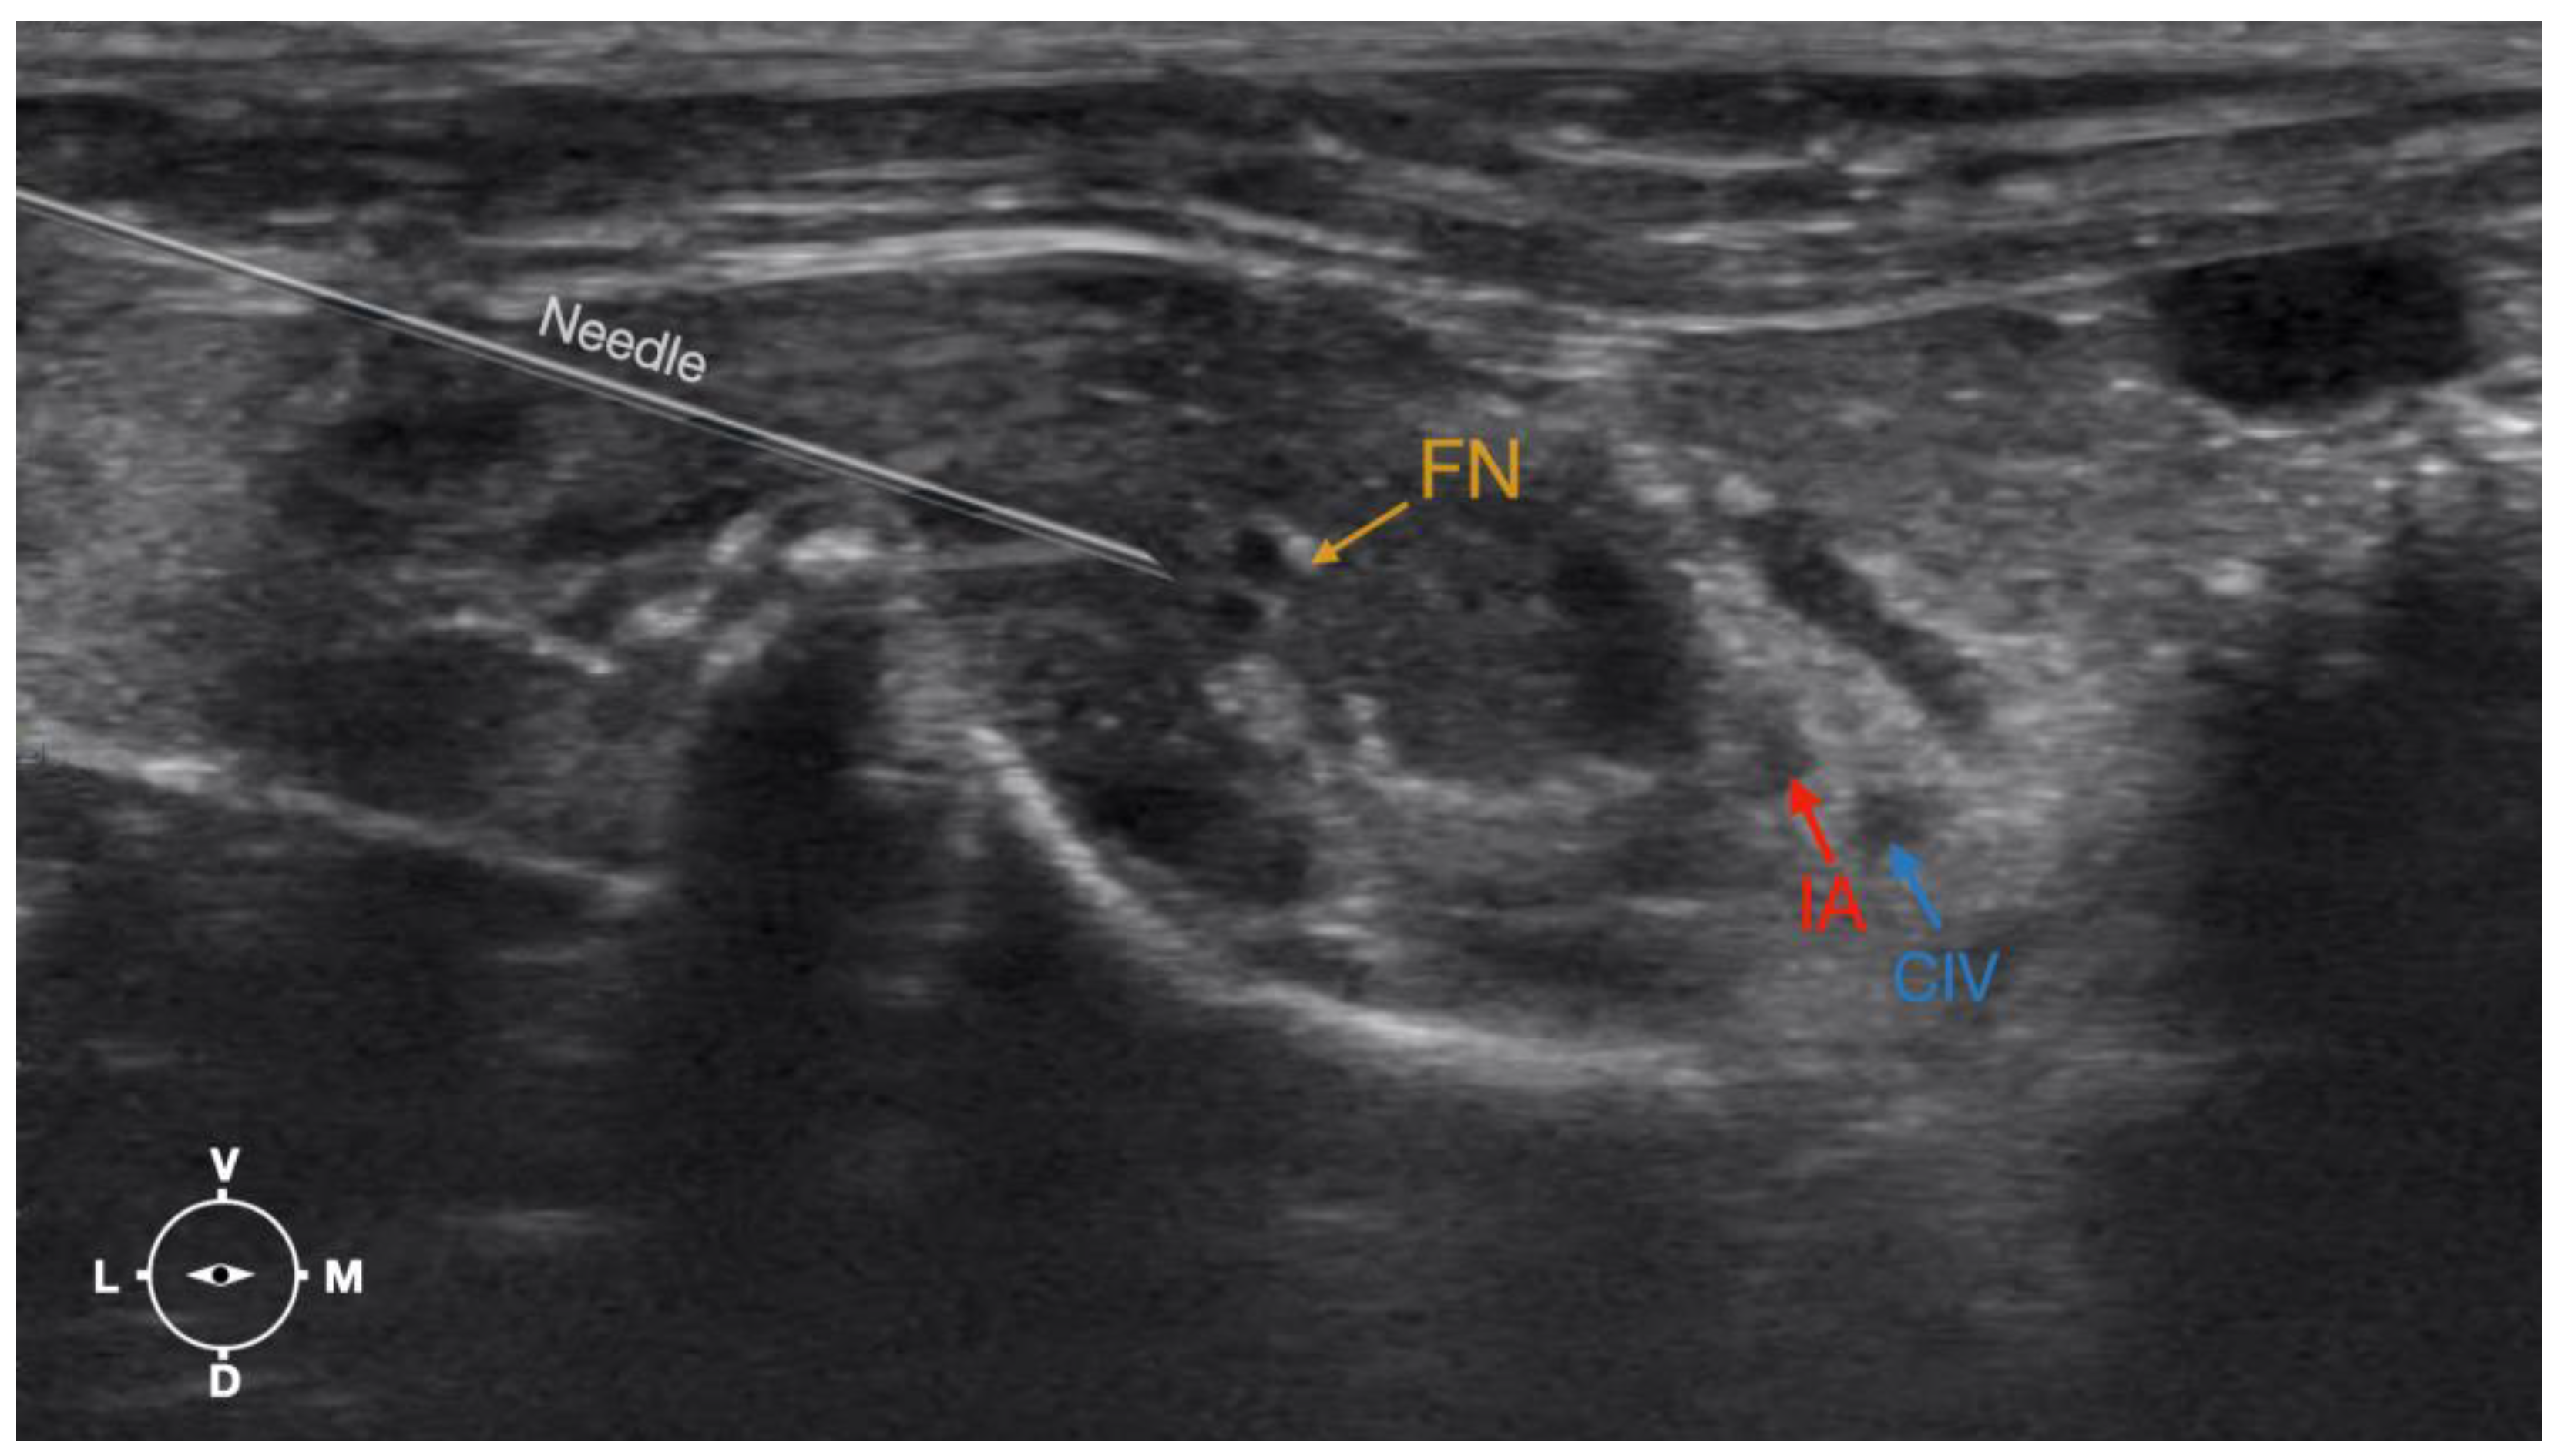

Figure 4. Corresponding transverse ultrasound image to Figure 5. The window of interest was set at a depth of 2 cm and the focus was at the level of the femoral nerve to optimize the image quality. The ultrasound image shows the FN and related structures. IA, iliac artery, CIV, common iliac vein; FN, femoral nerve; D, dorsal; L, lateral; M, medial; V, ventral.

2.3.2. Femoral Nerve Injection

The cadaver was positioned in dorsal recumbency before the leg was extended caudally. The transducer was placed over the hypaxial muscles, transverse to the long axis of the spine, and at the level of the projection of the iliac crest. The window of interest was set at a depth of 2 cm to optimize the image. Then, the transducer was moved in caudal direction along the IPM until the femoral nerve was clearly seen in the substance of the IPM (Figure 4). A 50 mm 22-gauge insulated needle (Sonoplex Stim Cannula, Pajunk Medical Produkte GmbH, Germany) prefilled with a L-NMB solution was inserted using an in-plane approach. The needle was inserted at the lateral edge of the transducer and advanced in-plane under sonographic guidance through the iliac fascia and IPM in a dorso-medial direction towards the femoral nerve (Figure 5 and Figure 6). The needle was advanced until its tip was located in vicinity of the femoral nerve. A test volume of 0.05 mL of L-NMB was injected to confirm adequate distribution. The remaining volume of 0.15 mL/kg was then injected extraepineurally around the femoral nerve.